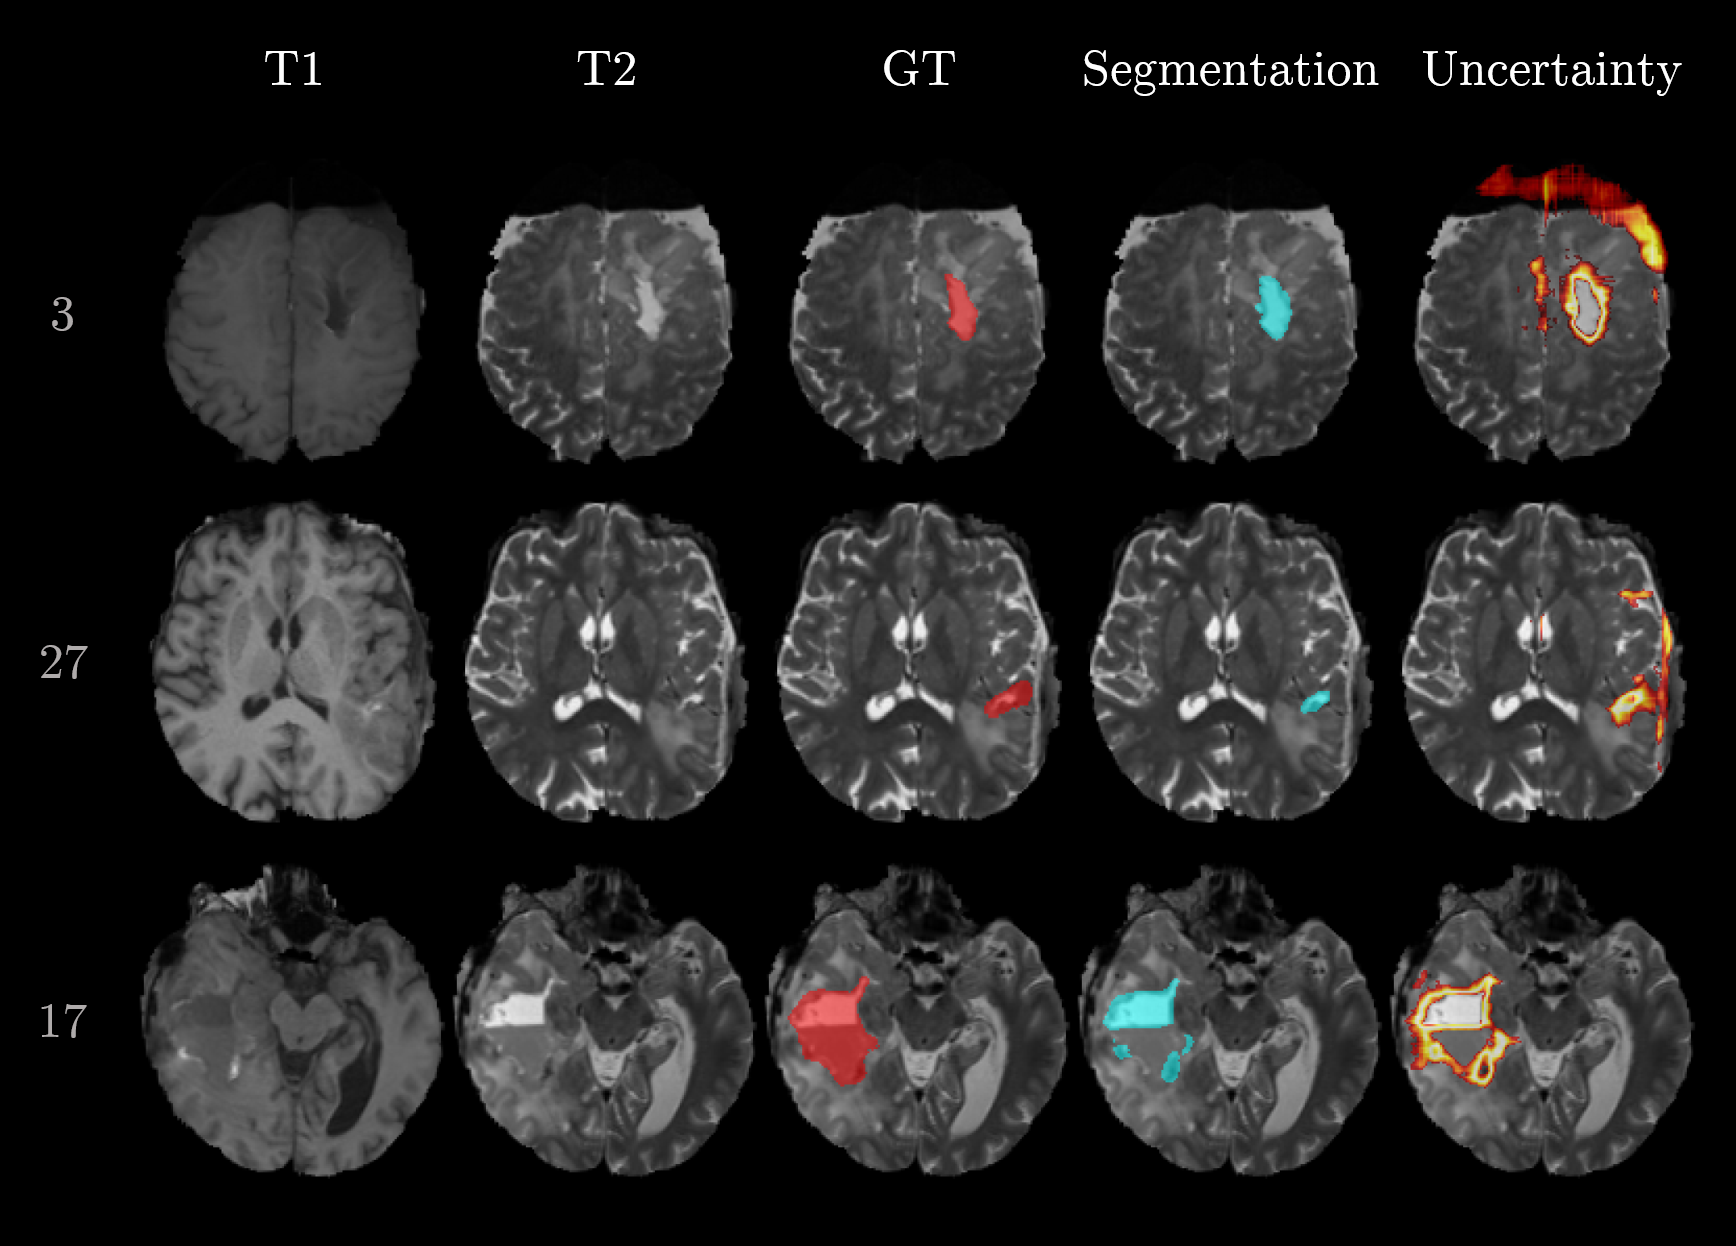

Figure 3 visualizes the segmentation results for the selected samples. The first and second row correspond to the best-performing cases. Their segmentation is close to ground truth and the uncertainty is mainly present at the boundary between foreground (i.e., cavity) and background. In contrast, samples 2, 24, and 10 show the worst performances. The network is struggling with the inhomogeneous cavity of sample 2. There is no clear delineation in the input sequences, which makes the task difficult. Sample 24 is most probably flawed because of the erroneous registration (compare T1 and T2 in Figure 3). Sample 10 is failing although the cavity is clearly visible in the T1 and T2 sequence. Further analysis of this case pointed to a particular hypointense cavity in the FLAIR sequence which appears isointense to cerebrospinal fluid and might confuse the network. Additionally, all three cases yielded increased uncertainties.

Refer to caption

Figure 3: Exemplary cases of segmented postoperative brain tumor cavities. The row numbers on the left correspond to the sample number. The two top rows show the best performing cases and the three bottom rows the worst cases. Columns represent the type of information (input sequences T1 and T2, ground truth (GT), and the network outputs, i.e., segmentation and uncertainty). The input sequences T1c and FLAIR are omitted.

In addition to the qualitative examples in Figure 3, Figure 5 focuses on examples situated in the false positives quadrant (sample 3 and 17) and false negatives quadrant (sample 17). The massive brain shift of sample 3 (top row in Figure 5) does not cause the segmentation to fail but is resulting in an increased uncertainty. Likewise, the uncertainty is increased at the meninges and subarachnoid space for sample 27. Both cases lead to large doubt scores because of the high uncertainties located far away from the segmented cavity. In contrast, sample 17 does mainly show uncertainty around the erroneous segmentation which leads to a small doubt score.

Figure 5: Examples of segmented postoperative brain tumor cavities. The row numbers on the left correspond to the sample number. The two top rows correspond to samples with high doubt scores and Dice coefficients (false positives). The bottom row corresponds to a sample with low doubt score and Dice coefficient (false negative).